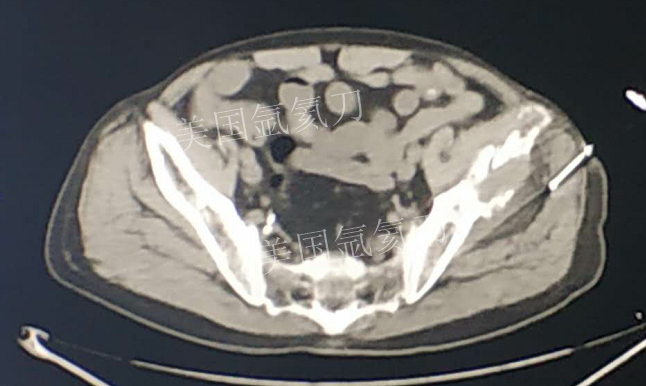

73岁臀部氩氦刀冷冻消融